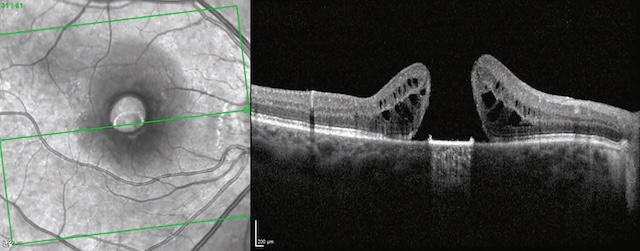

Les premiers signes de toxicité apparaissent dans la région juxtamaculaire où la densité pig-mentaire est particulièrement importante. L’atteinte toxique débute par une atteinte périfo-véolaire (qui épargne la fovéa), respectant ainsi l’acuité visuelle. L’atteinte débutante peut être détectée grâce à des examens complémentaires subjectifs nécessitant la collaboration du patient (champ visuel des 10° centraux retrouvant des scotomes juxtamaculaires et ERG multi-focal retrouvant une diminution des réponses périfovéolaires). Elle impose l’arrêt immédiat du traitement, car les mécanismes toxiques peuvent se poursuivre jusqu’à 6 mois après l’arrêt de la prise d’APS. En cas de poursuite du traitement, apparaît la maculopathie toxique aux APS en « œil de bœuf » visible au fond d’œil, en OCT et en angiographie (fig. 7.10). L’atteinte est alors irréversible.

A. Aspect de dégénérescence de l’épithélium pigmentaire périfovéolaire sur le cliché en autofluorescence. La région centrofovéolaire est épargnée, réalisant ainsi un aspect en cocarde dit en « œil de bœuf ». B. Sur la coupe OCT correspondante, on observe une atrophie de l’épithélium pigmentaire et de la rétine externe dans les régions immédiatement périfovéolaires. La région centrofovéolaire reste encore préservée (astérisque).

La partie A montre une image en autofluorescence du fond d’œil avec un aspect typique de maculopathie en œil de bœuf : une zone centrale de relative préservation entourée d’un anneau circulaire d’atteinte de l’épithélium pigmentaire rétinien. La partie B correspond à une coupe en tomographie en cohérence optique (OCT) montrant des altérations anatomiques de la macula, avec amincissement et désorganisation des couches rétiniennes externes. Deux flèches blanches indiquent les zones de lésion de la couche des photorécepteurs, tandis qu’un astérisque signale un amincissement central.